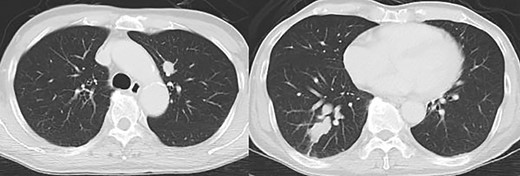

Contrast-enhanced computed tomography revealed a giant irregular mass (45 × 35 mm) in the abdominal wall (Fig. 2). No other intra-abdominal neoplasm were present; however, an irregular lung mass measuring 50 mm in size in the S10 region of the right lobe and a mass measuring 12 mm in size in the S1/2 region of the left lobe were found (Fig. 3). Total gastrointestinal endoscopy, including capsule endoscopy, revealed no neoplasm in the intestinal tract (Fig. 4a–c).

Computed tomography showed irregular mass at the abdominal wall.